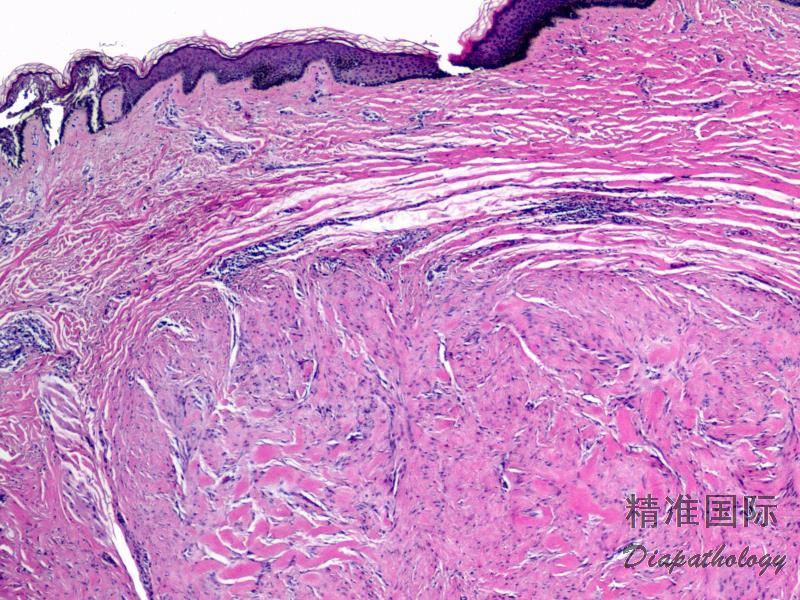

病变位于真皮内,由大量排列紊乱或纵横交错的致密粗大而深嗜伊红的胶原纤维组成,总体上有平行于表皮排列的趋势,表皮常表现为萎缩;

胶原纤维内可见温和的纤维母细胞,病变的早期在胶原纤维之间可见丰富的血管化间质,后期随着病变的进展可逐渐延伸并取代皮肤附属器结构,纤维母细胞和血管化间质明显减少,胶原纤维玻璃样变明显可伴有钙化或骨化;